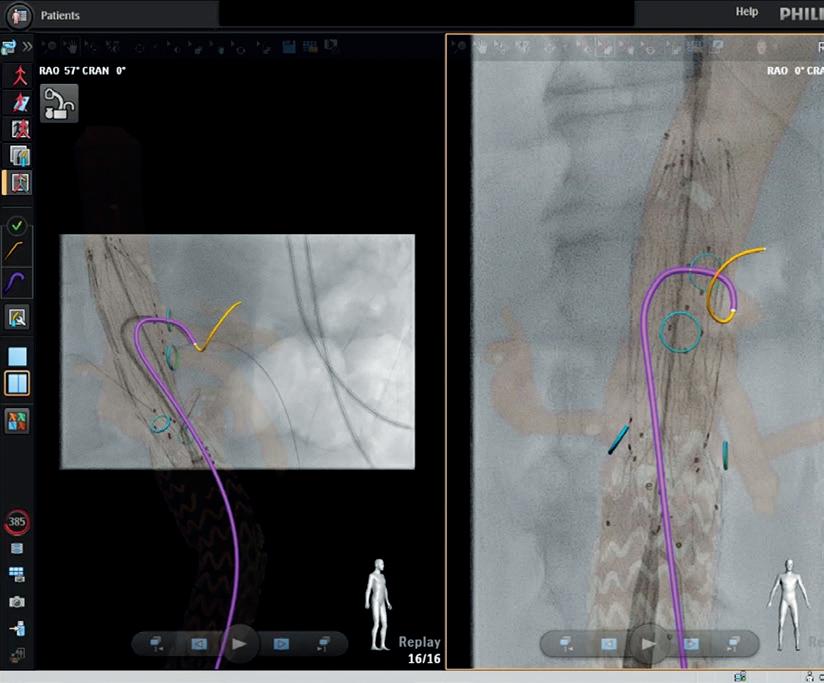

THIS ADVERTORIAL IS SPONSORED BY PHILIPS

Fibre optic technology shows “transformative” potential in endovascular aortic procedures

Two early adopters of Fiber Optic RealShape (FORS; Philips) share their expert opinions on the developing technology, highlighting its future potential in reducing radiation and increasing procedural efficiency.

The European Society for Vascular Surgery (ESVS) 2023 clinical practice guidelines on radiation safety1—the first recommendations on the topic to be published in the vascular surgery domain—brought into sharp focus the need to address radiation exposure during endovascular aortic procedures.

Bijan Modarai (Guy’s and St Thomas’ NHS Foundation Trust and King’s College London, London, UK), lead author of the guidelines, notes that X-ray-guided endovascular procedures have become the “mainstay” treatment modality for patients with vascular disease. X-ray is the current standard of care for endovascular procedures, he says. However, it has drawbacks, and the associated radiation poses a threat to patients and operators alike. Based on extensive research into radiation-induced DNA damage, Modarai and colleagues at King’s College London have identified biological evidence that radiation is having a negative effect on both patients’ and operators’ cells.

A “novel way” to visualise and navigate the aorta

Van Herwaarden states that he and two other operators have now performed a combined total of around 150 cases with FORS at the University Medical Center Utrecht. “We are getting used to it,” he says, noting that the team have seen improvements with

For Modarai, fibre optic technology represents a positive addition to his aortic practice. “The fact that you can visualise the catheter and the wire relying on this technology rather than X-ray is a conceptual advance,” he says. The benefits of the technology, in Modarai’s view, are multifactorial, pointing to its potential to protect both the patient and the operator from radiation, whilst also providing a “novel way” to visualise and navigate the aorta. “You get a view of the area that you are navigating in multiple planes,” he explains, “and that in itself also facilitates the procedure, allowing the entire team in the hybrid operating theatre to be able to follow what is going on and to be able to visualise what is being done on the screen”.

With regard to the literature on FORS, the evidence base is growing. Most recently, Eric J Finnesgard (University of Massachusetts Chan Medical School, Worcester, USA) and colleagues, under the senior authorship of Andres Schanzer, outlined an initial single-centre experience using FORS guidance in complex endovascular aortic repair. In November 2022, they reported online in the Journal of Vascular Surgery that FORS has shown “promise” in their aortic practice, with “acceptable technical success and reductions in procedural times and radiation usage”.2 Schanzer is set to share these findings, as well as his experience so far using FORS, at the Charing Cross (CX) Symposium 2023 (25–27 April, London, UK).

Van Herwaarden believes that FORS will have positive effects on radiation. He stresses, however, that this still has to be proven, which is why he and his team together with seven other renowned centres in Europe and the USA are conducting a registry study. “We are now busy with the analysis of the more than 600 cases that have been done,” he explains.

While data are being collected, van Herwaarden is keen to stress that FORS is still in its early stages. “It feels like we are still in the beginning of a new technology that is slowly proving itself,” he remarks, and is looking ahead to a “promising” future where FORS could enable less need for radiation, quicker procedures, and fewer complications.

The ESVS guidelines aim to raise awareness of the risks of radiation and provide guidance on best practice, closing with a forward-looking chapter on the importance of new and future technologies in reducing and, in the longer term, eradicating the need for radiation. Fibre optic guidance is one such technology, with reference made not only to its radiation-reducing potential, but also to how it might enhance visualisation of catheters and wires and lead to potentially shorter procedure times.1,2

Joost van Herwaarden (University Medical Center Utrecht, Utrecht, The Netherlands), who led the firstin-human clinical feasibility study of endovascular navigation with FORS,3 notes that mention of the technology in the guidelines is important for the purpose of generating awareness and interest among the vascular community. “All of us should be aware that there are other possibilities than just using

the technology in the three years since they started using it. He mentions that with the recent introduction of Philips’ 3D Hub technology, for example, it is possible to use many different commercially available catheters and show them with the FORS technology.

The team now use FORS weekly and in “almost all endovascular aneurysm repairs,” van Herwaarden details. Specifically, he tells Vascular News that FORS “really gives you a better understanding of the position and 3D morphology of the devices in the 3D anatomy or workspace,” noting that the better view the technology provides makes cannulations easier.

According to van Herwaarden, the future of FORS lies also in its combined use with other emerging technologies, for instance robotic tracking, artificial intelligence, and intravascular ultrasound (IVUS), with the combination offering “an even greater promise for simplifying complex procedures and realising radiation dose reduction for patients and for staff”.

Modarai believes the technology will be “transformative” in endovascular aortic procedures, while adding the caveat that there is still some way to go. He looks ahead to iterative improvements with regard to compatible wires and catheters, and the footprint of the ancillary devices, for example, which will make fibre optics “easier and easier” to incorporate into clinical practice. Eventually, he hopes, it will become an “essential” part of the workflow, allowing operators to circumvent the use of X-rays for endovascular procedures. “When that goal is reached, then it is difficult to imagine that one would want to perform these procedures without a technology like this.”

L-R: Bijan Modarai conducting a FORS case (image courtesy of Guy’s and St Thomas’); Cannulation of the coeliac trunk in fenestrated endovascular aneurysm repair (image courtesy of UMC Utrecht). Bijan Modarai Joost van Herwaarden